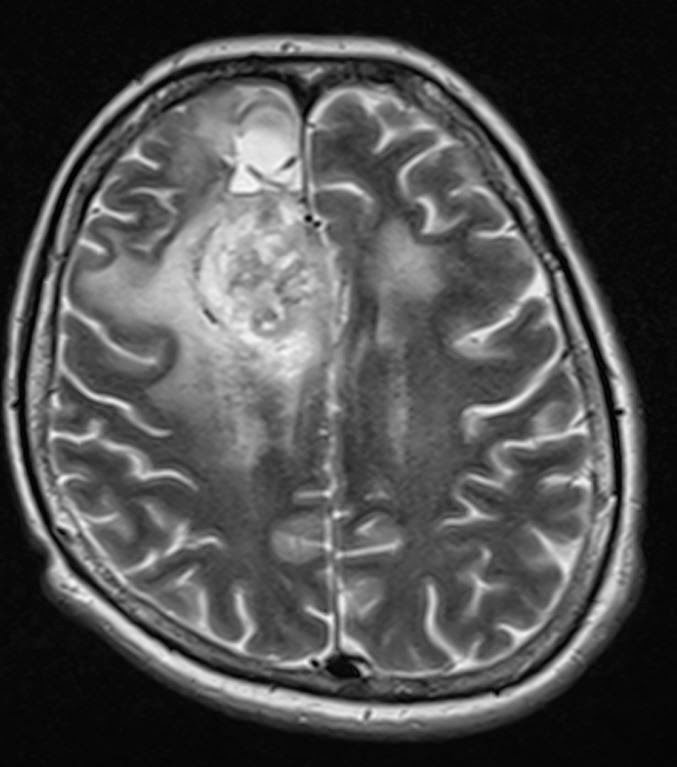

Összehasonlítva a 2014.02.10-i MR vizsgálattal:

A középvonalat balra kb. 1,5 cm-rel meghaladó és a corpus callosumot involváló jobb oldali frontalis inhomogén szerkeszetű és halmozású elváltozás mérete minden irányban mérsékelten csökkent, legnagyobb átmérője jelenleg kb. 5,6 x 5 x 4,7 cm. T2 súlyozásnál a laesio körül a hyperintenzitás kiterjedése főként dorsalis irányban enyhén csökkent. Az elülső frontalis műtéti behatolás mögött parasagittalisan a liquorhoz viszonyítva magasabb jelű bennéket tartalmazó cystosus elváltozás mérete hasonló a korábbihoz. Bal oldalon temporalis DVA* látható. A kamrarendszer frontális részeinek compressioja és dislocatioja lényegesen nem változott.

Vélemény: Enyhe méretcsökkenést mutató jobb túlsúlyú bifrontális tu. a corpus callosum infiltratiojaval.

*DVA: developmental venous anomaly (DVA) = cerebral venous angioma

Fejlődési eredetű (embrionális) vénás anomális = agyi vénás angióma (érdaganat)

Elkészült a kemoterápia alatti első MR-felvétel, és íme az eredménye:

Saját, műkedvelő fordításomban ez azt jelenti, hogy:

Jobb oldalon a corpus callosum, azaz kérgestest, amely nem más, mint a két agyféltekét összekötő rostköteg, és a gyrus cinguli, azaz az agyféltekék mediális, tehát középen elhelyezkedő felszínén található hosszú hajlított struktúra elülső részében elhelyezkedő térfoglalás nagysága érdemben nem változott, azonban a szélei jobban elhatárolódtak.

A mérsékelt fokú (hoppá! csak mérsékelt!!!) baloldali terjedés és a környező részben ödémás terület olyan, mint november 11-én volt. Az elülső és a frontális szarvak jobbra, lefelé nyomódtak össze. Továbbá az elülső szarvak hátsó fele olyan, mint volt: mérsékelten tágultak jobb túlsúllyal.

Ami jó hír: mérséklődött a középvonal balra íveltsége.

Mindazonáltal a jobb oldali árkok jobban ábrázolódnak.

A műtéti üreg a korábbihoz hasonló! Nem nőtt tovább a rohadék!!!

Az orvosi vélemény: Stabil állapot.